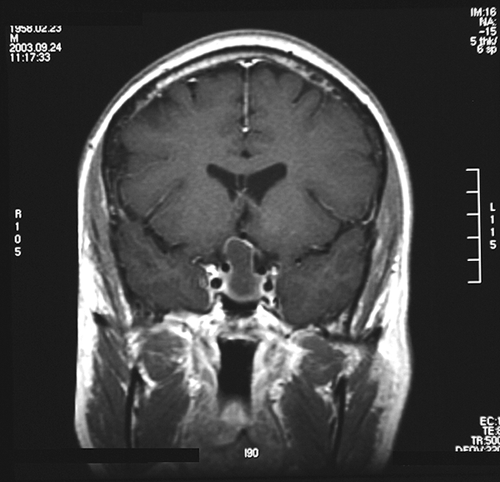

Clinical informationThe patient was a 45 year-old man who presented with staring episode that is reminiscent of a seizure. MRI examination disclosed a cystic sellar mass that deflected his optic nerve. There was no clear visual loss.

Com403-1-MRI1.gif (175407 bytes) Com403-1-2.gif (140093 bytes) Com403-1-4.gif (125178 bytes) Com403-1-1.gif (139689 bytes) Com403-1-3.gif (145349 bytes)